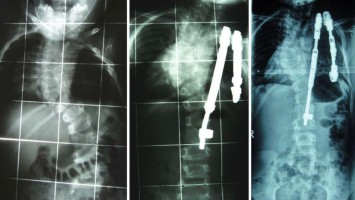

Frühe Skolioseoperation verbessert nicht die Lungenfunktion

Die frühe, wachstumsadaptierte Operation skoliotischer Fehlbildungen der Wirbelsäule hat in einer Studie keine positiven Wirkungen auf die Lungenfunktion ergeben. Allenfalls wurde einer Verschlechterung vorgebaut.

Tabletten werden in Hand geschüttet/© O.Farion / Stock.adobe.com (Symbolbild mit Fotomodell), Mann appliziert Salbe auf sein Knie/© Ake Ngiamsanguan / Getty Images / iStock (Symbolbild mit Fotomodell), Cannabisarzneimittel/© [M] Rocky89 / Getty images / iStock, Störung der Lidhebung bei Myasthenia gravis/© Alessandro Grandini / stock.adobe.com (Symbolbild mit Fotomodell), Arzt untersucht Patient mit Rückenschmerzen/© gilaxia / Getty Images / iStock (Symbolbild mit Fotomodellen), Junger bärtiger Mann liegt im Bett und hält sich die Stirn/© kleberpicui - stock.adobe.com (Symbolbild mit Fotomodell), Vordere Kreuzbandruptur/© Springer-Verlag Berlin Heidelberg 2016, Liposarkom des Funiculus spermaticus/© Springer Medizin Verlag GmbH, Behandschuhte Hände drücken Stumpf nach Amputation/© Vitaly Zubrytsky / stock.adobe.com (Symbolbild mit Fotomodellen), Untersuchung des Beins eines Patienten/© Visionär / Fotolia, Mann erhält einen CT-Scan /© Mark Kostich / stock.adobe.com (Symbolbild mit Fotomodell), Arzt untersucht Senior am Rücken/© miodrag ignjatovic / Getty Images / iStock (Symbolbild mit Fotomodellen), Bildgebung verschiedener interstitieller Lungenerkrankungen/© Christoph Lederer et al. / all rights reserved Springer Medizin Verlag GmbH, Kleinkind und Teddy mit Verband/© simoningate / Getty Images / iStock (Symbolbild mit Fotomodell), Frau unkenntlich fasst sich ans Knie/© Pornpak Khunatorn / Getty Images / iStock (Symbolbild mit Fotomodell), Ein älteres Paar läuft mit Stöcken im Wald/© Roman / Stock.adobe.com (Symbolbild mit Fotomodell), Illustration zur künstlichen Intelligenz/© Toowongsa / Stock.adobe.com (Symbolbild mit Fotomodell), Ärztin untersucht Patientin mit Knieschmerz/© Jirapong / Stock.adobe.com (Symbolbild mit Fotomodell), Arzt untersucht älteren Mann/© contrastwerkstatt / Stock.adobe.com (Symbolbild mit Fotomodellen), Blutabnahme/© Yakobchuk Olena / stock.adobe.com (Symbolbild mit Fotomodell), Point-of-care-Ultraschall bei Trauma/© Vicent O et al. / all rights reserved Springer Medizin Verlag GmbH, Röntgenbild Kiefer/© Aniuszka / Fotolia (Symbolbild mit Fotomodell), Box mit Tabletten/© ekachai050050 / stock.adobe.com (Symbolbild), Manuelle Behandlung unterer Rückenschmerzen/© Viorika / Getty Images / iStock (Symbolbild mit Fotomodellen), Operationssaal-Korridor /© h368k742 / stock.adobe.com, Ohnmächtige ältere Frau/© Satjawat / stock.adobe.com (Symbolbild mit Fotomodellen), Akupunktur/© (M) geargodz / stock.adobe.com (Symbolbild mit Fotomodell), Hand greift nach Skalpell/© Morsa Images / Getty Images / iStock, Gruppe beim Rückentraining im Fitnesscenter/© Robert Kneschke / stock.adobe.com (Symbolbild mit Fotomodellen), Mann auf dem Bau/© pololia / Stock.adobe.com (Symbolbild mit Fotomodell), Psychotherapeutische Sitzung/© PeopleImages / Getty Images / iStock (Symbolbild mit Fotomodellen), Frau sitzt besorgt beim Arzt und hält sich den Kopf/© M+Isolation+Photo / Stock.adobe.com (Symbolbild mit Fotomodell), Seniorin liegt reglos auf Boden/© Racle Fotodesign / stock.adobe.com (Symbolbild mit Fotomodell), Medizinisches Personal hält verschiedenfarbige Kinesiotapes/© Татьяна Волкова / stock.adobe.com (Symbolbild mit Fotomodell), Ärztin in Op.-Kleidung/© shapecharge / Getty Images / iStock (Symbolbild mit Fotomodell), Skoliose/© Springer Medizin, Vordere Kreuzbandruptur/© Müller P E & Niethammer T R / all rights reserved Springer Medizin Verlag GmbH, Rettungsdienst/© huettenhoelscher / Getty images / iStock (Symbolbild mit Fotomodellen), Person hält zwei Tabletten in der Hand/© AsiaVision / Getty Images / iStock (Symbolbild mit Fotomodell), Video-Therapie /© Valerii Honcharuk / stock.adobe.com (Symbolbild mit Fotomodellen), Ältere Person hält sich das Knie/© ZayNyi / Stock.adobe.com (Symbolbild mit Fotomodell), Fallbeispiel Röntgenaufnahme des Thorax in zwei Ebenen/© Reinke L. et al. / all rights reserved Springer Medizin Verlag GmbH, Kleiner Junge nach Fahrradunfall/© JohnAlexandr / Getty Images / iStock (Symbolbild mit Fotomodell), Läufer umfasst sein Sprunggelenk/© PeopleImages / Getty Images / iStock (Symbolbild mit Fotomodell), Mann mit Knieschmerzen/© Rockaa / Getty Images / iStock (Symbolbild mit Fotomodell), Vorbereitung eines periphere Venenverweilkatheter/© Seppographie / stock.adobe.com, Springer Medizin Podcast - Stürze im Alter/© Gatz M et al / all rights reserved Springer Medizin Verlag, Orthese und Gehhilfen/© Ralf Geithe / stock.adobe.com (Symbolbild mit Fotomodell), Mann geht mit Hund an der Leine spazieren/© K. Thalhofer / stock.adobe.com (Symbolbild mit Fotomodell), Schenkelhalsfraktur prä- und postoperativ/© Henze K et al. / all rights reserved Springer Medizin Verlag GmbH, Älterer Arzt mit Arzthelfer schauen über Patientenakte/© stokkete / stock.adobe.com (Symbolbild mit Fotomodellen), Röntgenbild Hand/© Mathias Weil / stock.adobe.com, Hinweisschild Notaufnahme/© huettenhoelscher / Getty images / iStock, Frau sitzt vor mehreren Bildschirmen/© Baba Images / stock.adobe.com (Symbolbild mit Fotomodell), Junge Ärztinnen und Ärzte diskutieren/© fizkes / stock.adobe.com (Symbolbild mit Fotomodellen), Systemischer Lupus erythematodes Gesicht Mann/© velimir / Stock.adobe.com (Symbolbild mit Fotomodell), Operation Karpaltunnelsyndrom/© Gardinovacki / Getty Images / iStock (Symbolbild mit Fotomodell), CAR-T-Zellen/© Meletios Verras / Getty Images / iStock, Ärztin untersucht älteren Mann/© Drazen Zigic / Getty Images / iStock (Symbolbild mit Fotomodellen), Frau zieht Patientin Thrombosestrumpf an/© tibanna79 / stock.adobe.com (Symbolbild mit Fotomodellen), Wirbelsäulen-MRT bei Patient mit axialer Spondyloarthritis/© Springer Medizin, Frau bei Knochenmineraldichte-Messung/© gelmold / stock.adobe.com (Symbolbild mit Fotomodell), Psoriasisarthritis /© Springer Medizin, Anatomischer Überblick Handgelenk/© Deglmann CJ / all rights reserved Springer Medizin Verlag GmbH, Frau mit Hut im Wald/© (M) encierro / stock.adobe.com (Symbolbild mit Fotomodell), Rheumatoide Arthritis in den Händen/© RFBSIP / stock.adobe.com (Symbolbild mit Fotomodell), Frau und Mann joggen im Wald/© Harbucks / Getty Images / iStock (Symbolbild mit Fotomodellen), Frau mit Knieschmerzen/© shurkin_son / Getty Images / iStock (Symbolbild mit Fotomodell), Hallux valgus/© masanyanka / stock.adobe.com, Raucher Zigarette Rauch /© buenaventura13 / stock.adobe.com (Symbolbild mit Fotomodell), Magnetresonanztomographie/© Svitlana / Stock.adobe.com (Symbolbild mit Fotomodell), Anästhesistin im OP/© stefanamer / Getty Images / iStock (Symbolbild mit Fotomodellen), Verband an Unterschenkelstumpf wird angelegt/© angkhan / stock.adobe.com (Symbolbild mit Fotomodellen), Schreiendes Baby/© AzmanL / Getty Images / iStock (Symbolbild mit Fotomodell), Narbe nach Kniegelenkersatz/© Miriam Dörr / Fotolia (Symbolbild mit Fotomodell), Mann untersucht Frau an der Lende/© pololia / stock.adobe.com (Symbolbild mit Fotomodell), Gebrochener Arm eines Kindes erhält Gips/© Rafael Ben-Ari / stock.adobe.com (Symbolbild mit Fotomodellen), Unikompartimentelle Knieprothese/© NICOLAS LARENTO / stock.adobe.com, Frankfurt am Main an einem heißen Sommertag mit strahlender Sonne und großem Thermometer/© Günter Albers / Stock.adobe.com, Infantiles Hämangiom/© tolgart / Getty Images / iStock (Symbolbild mit Fotomodell), Zecke auf menschlicher Haut/© sasel77 / stock.adobe.com, Urinbecher und Urinanalyse-Streifen/© RHJ / Stock.adobe.com, Walking mit Kniebandage/© Suzi Media Production / Getty Images / iStock (Symbolbild mit Fotomodell), Fraktur der lateralen Condyle des Humerus im Röntgenbild/© Susmit / stock.adobe.com, Arzt untersucht Knie einer Seniorin/© FluxFactory / Getty Images / iStock (Symbolbild mit Fotomodellen), Röntgenbild einer Psoriasis-Arthritis/© Springer Medizin Verlag GmbH, Frau macht Gymnastikübung in ihrem Schlafzimmer/© Krakenimages.com / stock.adobe.com (Symbolbild mit Fotomodell), Abklärung von Rückenschmerz bei älterer Patientin/© andreswd / Getty Images / iStock (Symbolbild mit Fotomodellen), Physiotherapeut behandelt Patientin an Schulter/© © contrastwerkstatt / stock.adobe.com (Symbolbild mit Fotomodellen), Wald/© alexugalek / stock.adobe.com, Arthropedia, Kinesiotape um das Knie herum/© baranq / stock.adobe.com (Symbolbild mit Fotomodell), Röntgenbild eines künstlichen Hüftgelenks/© Nicolas Larento / Fotolia, Prähabilitation am Fußgelenk/© herraez / Getty Images / iStock (Symbolbild mit Fotomodellen), Junge Ärztin vor einem Triage-Zelt/© Milos / Stock.adobe.com (Symbolbild mit Fotomodell)